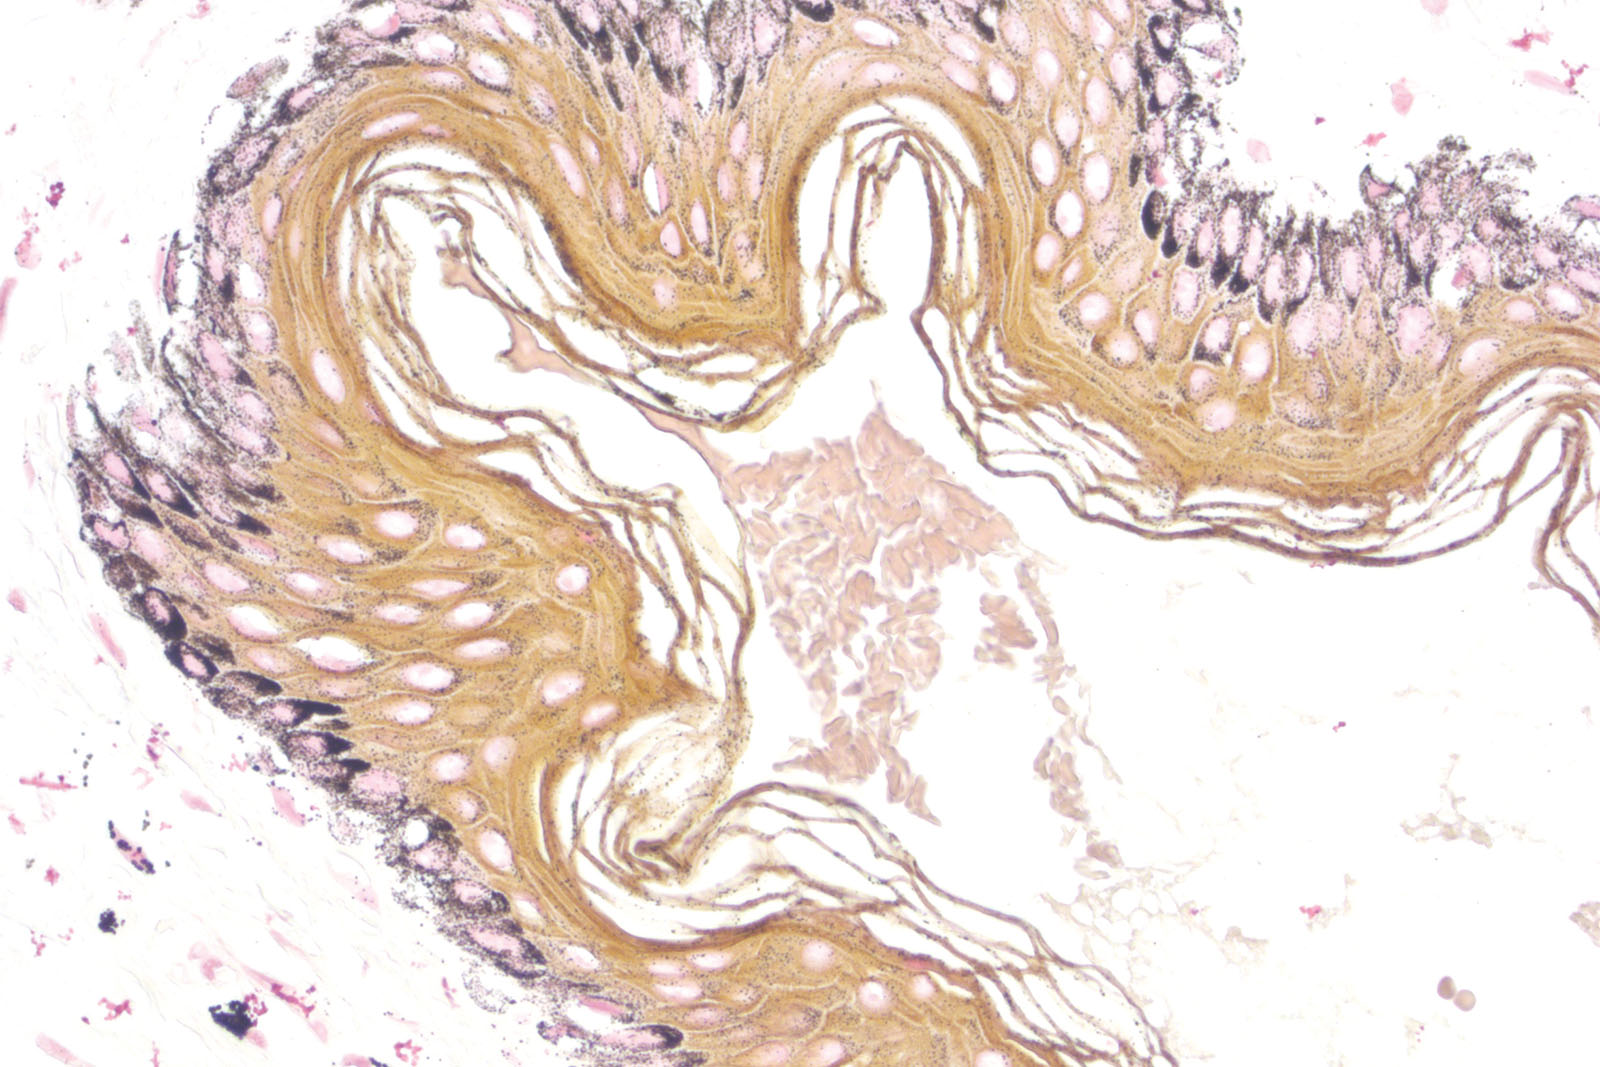

Masson Fontana kit is used in a specific method for proving argentaffin granules in histological sections, based on the reduction of silver nitrate to elemental silver. Melanin is a pigment usually found in skin, hair, retina, and some parts of the central nervous system. In order to avoid getting false-positive results, BioGnost’s Masson Fontana kit contains reagents for melanin depigmentation. Depigmentation is conducted on a control section before silver impregnation.